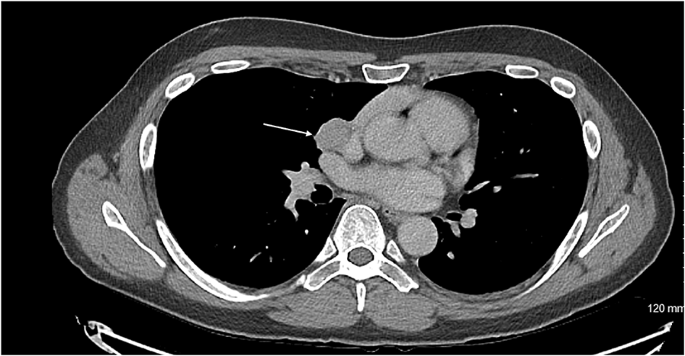

Axial CT showing the carcinoid tumour (demonstrated by arrow) in close proximity to innominate vein

A DOTATATE PET CT scan showed recurrence of his thymic carcinoid at the level of the groove between the right main pulmonary artery and right atrium, growing very close to the phrenic nerve. It was advised for him to undergo complete excision of the lesion requiring a joint approach from cardiac and thoracic surgeons. The patient subsequently underwent a median sternotomy, removal of recurrent mediastinal tumour invading the pericardium and wedge resection of the lung, lymph node sampling.